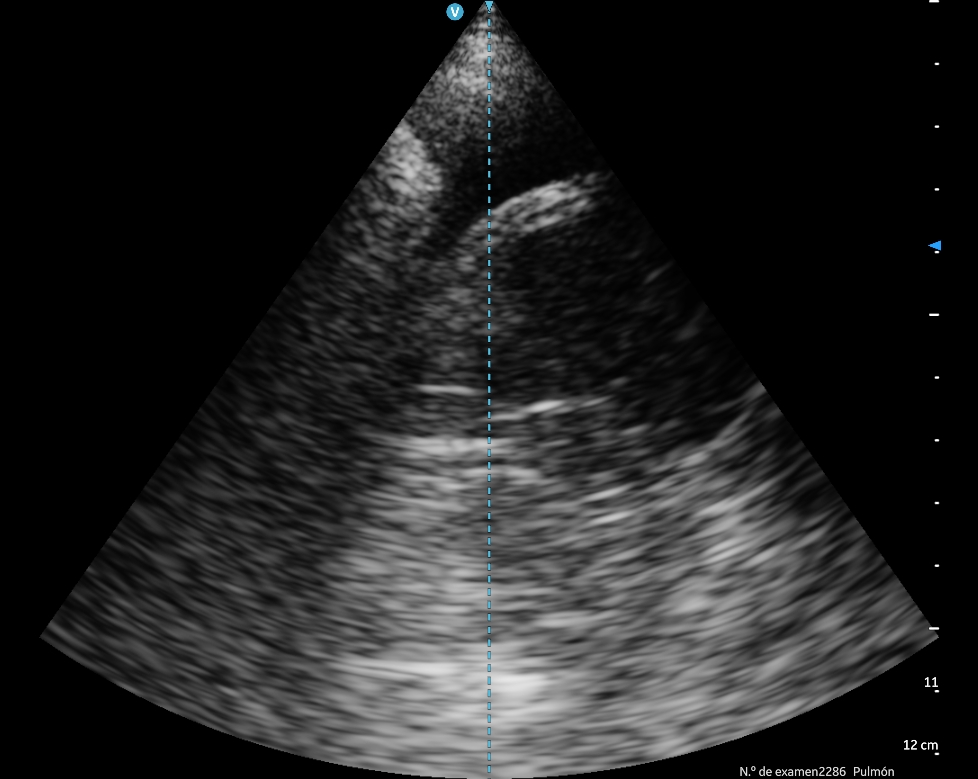

Ecografía pulmonar muestra imagen anecóica escasa en seno costofrénico izquierdo, compatible con líquido en cavidad pleural. Base pulmonar derecha evidencia patrón C compatible con consolidación neumónica.

La ecografía pulmonar demostró ser una herramienta diagnóstica de gran utilidad en el abordaje inicial del paciente con disnea en el servicio de urgencias. Su aplicación permitió identificar de manera rápida hallazgos importantes como la presencia de líquido pleural y la consolidación pulmonar compatible con neumonía, complementando y reforzando la información obtenida en la anamnesis y en la exploración física.